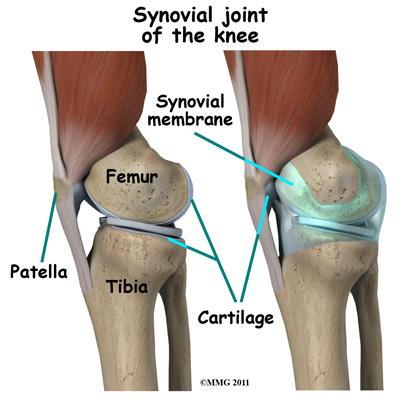

The knee joint is surrounded by a water-tight pocket called the joint capsule.

This capsule is formed by the knee ligaments, connective tissue, and synovial tissue. When the joint capsule is filled with sterile saline and is distended, the surgeon can insert the arthroscope into the pocket that is formed, turn on the lights and the camera, and see inside the knee joint as if looking into an aquarium. The surgeon can see nearly everything that is inside the knee joint including: (1) the joint surfaces of the tibia, femur and patella, (2) the two menisci, (3) the two cruciate ligaments, and (4) the synovial lining of the joint.